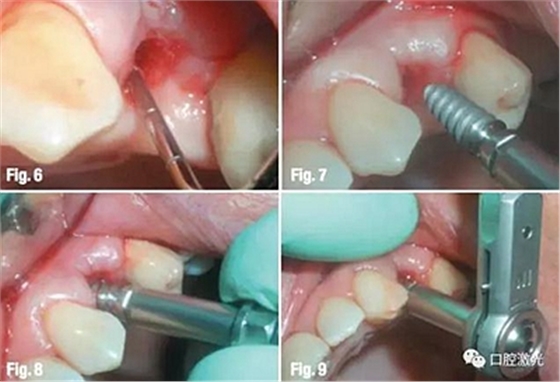

當(dāng)?shù)竭_(dá)適合深度后,再沿水平方向適當(dāng)延伸。先手動(dòng)安裝種植體,在利用扭力扳手設(shè)定為廠家推薦最大扭矩進(jìn)行安裝,直到將種植體安裝牢固。

隨后,設(shè)置激光參數(shù)為功率2W、脈沖能量100mJ、20%水、20%氣,對(duì)手術(shù)區(qū)域附近進(jìn)行牙齦整形,以便于取模。隨后設(shè)置激光功率為1W、脈沖能量50mJ、10%水、10%氣,對(duì)種植體周圍軟組織進(jìn)行輕度去角質(zhì)化處理。整個(gè)預(yù)備和取模的時(shí)間不超過15分鐘,因此種植體穩(wěn)定度極高。